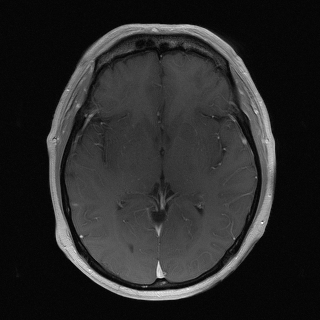

Brain MRI (Axial T1 Post-contrast)

Edema, mass, posttreatment change